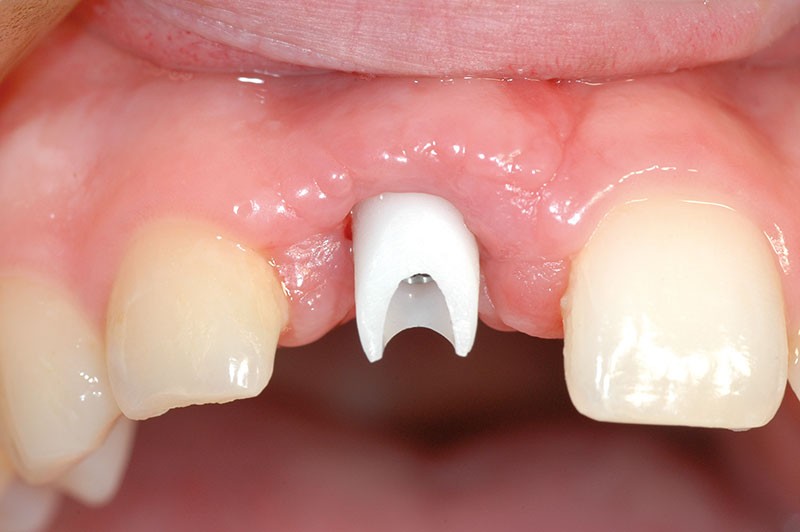

L’implant a été posé alors que la patiente était âgée de 17 ans (le 13 août 2004), à la suite d’un traumatisme entraînant la perte de cette dent (fig. 2a à d), puis la couronne a été posée 5 mois plus tard (le 7 janvier 2005).

Nous proposons de retirer la couronne et le pilier implantaire, d’effectuer une greffe de tissu conjonctif enfouie afin d’améliorer le volume du tissu kératinisé péri-implantaire [5] et de procéder à la pose d’une couronne provisoire transvissée (fig. 3a à h).